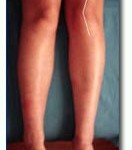

La siguiente imagen nos muestra unas rodillas con pocas posibilidades de sufrir patología rotuliana. La última nos muestra la técnica artroscópica de Detrisac con apertura del alerón externo y plicatura del interno.